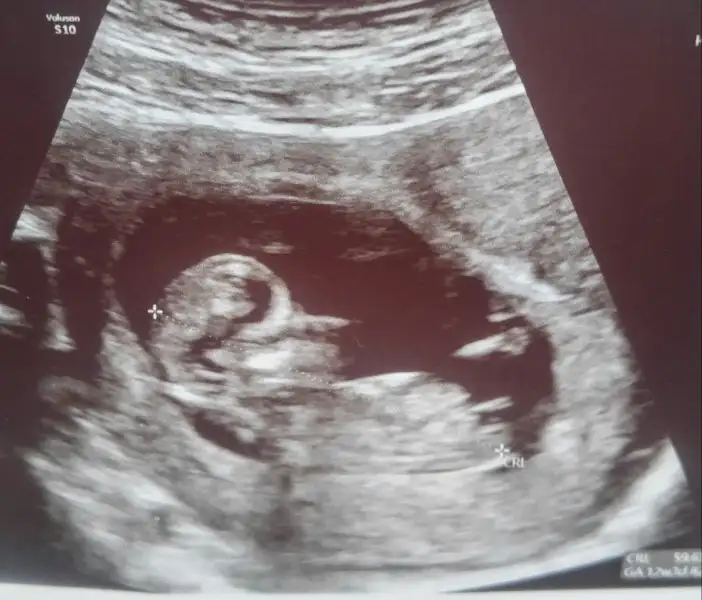

Güzel anneler merhaba kaç gündür yoğunun hiç giremedim o kadar mesaj birikmiş ki bakalım inşallah okuyabilirim hepsini :) biz de bugün kontrole gittik benim minik biraz annesine çekmiş sanırım uyuşuk çıktı. Sabah gittiğimizde doktor istediği pozisyona getiremedi baya zorladı ama ı-ıh yok kıpırdamadı. Ben de yemek yedim çikolata falan yedim öyle bir daha girdim, çok şükür kıpır kıpırdı ense kalınlığımız normalde çıktı. Ellerini parmaklarını gördüm çok güzel bir duyguydu. Ayrıca doktorumuz kız gibi ama tabii acele etmeyin alışveriş için dedi. İçimden hep kız geçiyordu umarın süpriz yapıp anne ben aslında erkeğim demez :) hepinize güzel günler diliyorum:)